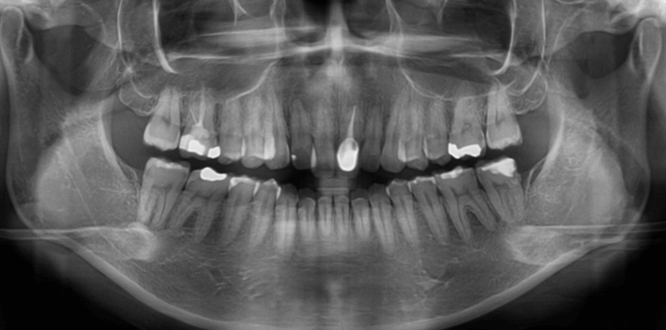

| 年齢・性別 | 22歳女性 |

|---|---|

| 主訴 | 上下顎前歯部に開咬と口元の突出感を気にされて来院された22歳女性。咬み合わせや審美的な改善を希望されていました。 |

| 治療期間・回数 | 3年9ヶ月・32回 |

| 費用 | 930,000円 |